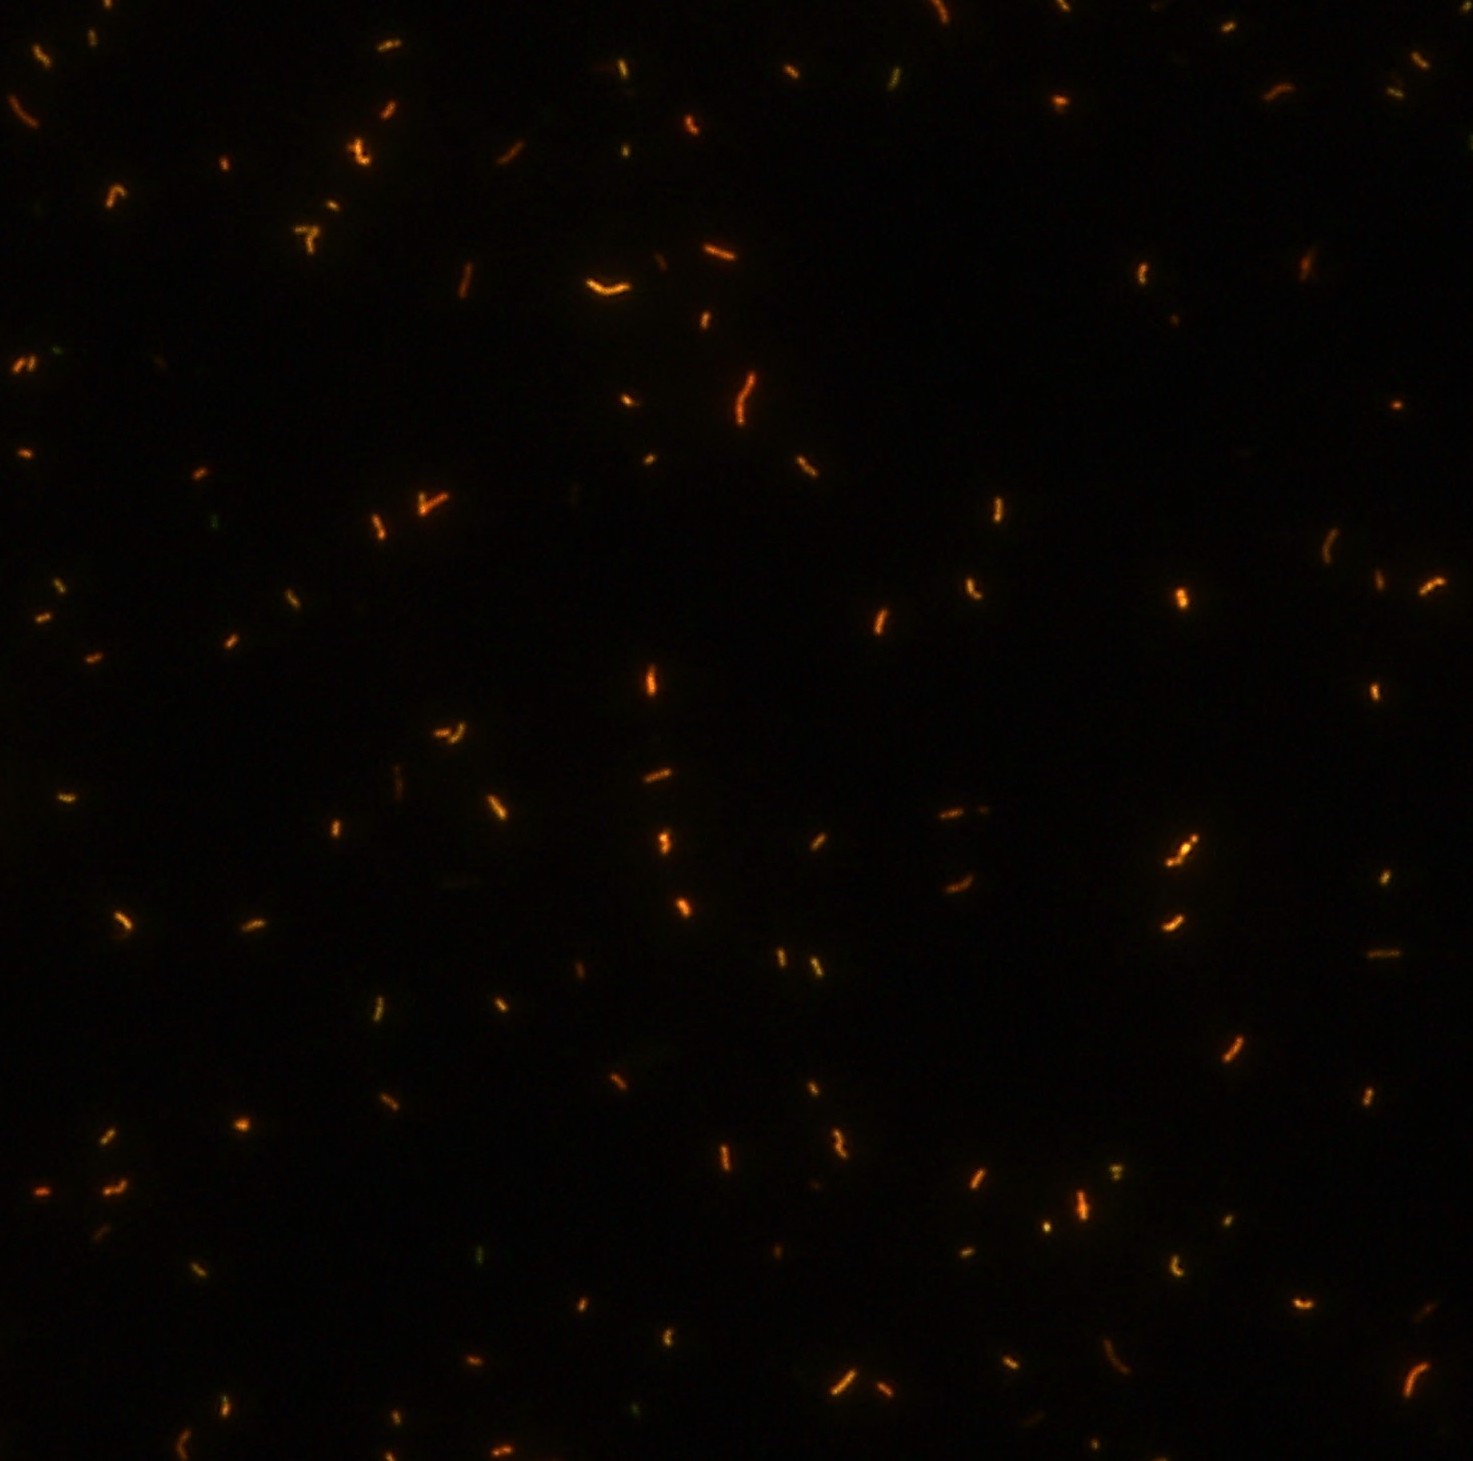

顯微染色技術是檢測結核桿菌方法之一。分枝桿菌細胞壁中含有分枝菌酸,其可以與染料牢固結合,具有“抗酸性”的特征。熒光染料金胺-羅丹明在染色中與抗酸生物細胞壁內的分枝菌酸相結合,并耐受酸醇(脫色劑)清洗脫色。反染色劑高錳酸鉀被用來顯出染色生物。AFB(熒光)染色試劑盒設計既可用于自動染色機,也可用于手工染色。產品穩定性好,染色效果佳。

染色結果 (熒光法×400)

用于分枝桿菌、諾卡菌等細菌抗酸染色,包括熒光染色。